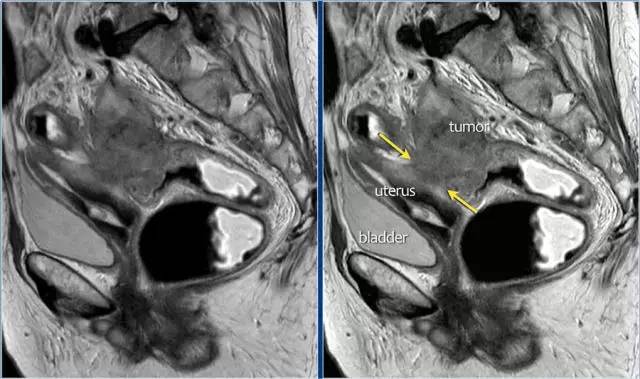

T4b 分期,侵入周围器官

T4 期肿瘤侵犯周围结构,如盆壁、阴道、前列腺、膀胱或精囊,这类局部晚期患者需要进行长程放化疗和广泛切除。

图 16 在矢状 T2W 图像上,直肠和阴道后壁之间有脂肪平面的损失。在轴向图像上,看到肿瘤的相对低的信号强度延伸到阴道的后壁(箭头)

以下 5 幅图例请连续观看:

图 17~21 肿瘤的低信号强度延伸到阴道的后壁(箭头)

图 22 浸润到子宫后壁的肿瘤